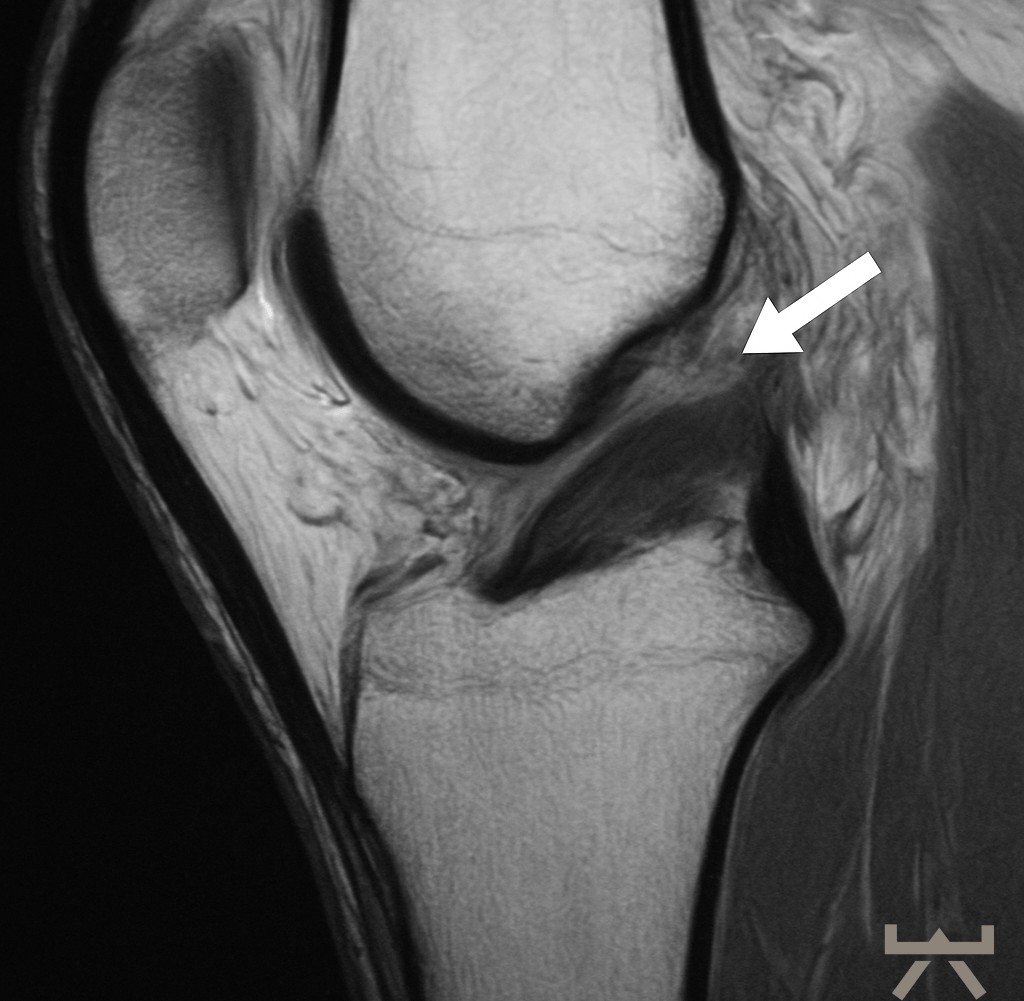

- MRT

- (CT)

Durch die Schwellung ist die Diagnostik in der Bildgebung jedoch erschwert, daher muss diese nach dem Trauma schnellstmöglich erfolgen oder es kann eine wiederholte Untersuchung in der subakuten Phase sinnvoll sein. Hierfür eignen sich die oben aufgelisteten bildgebenden diagnostischen Mittel, wobei das MRT hier die erste Wahl ist. In diesen Untersuchungen werden die nötigen Strukturen des Knies dargestellt. Auch häufige Begleitverletzungen wie Meniskusschäden oder Verletzungen des Außenbandes können in der Magnetresonanztomographie direkt ausgeschlossen/diagnostiziert werden.

Trotzdem muss man berücksichtigen, dass bildhafte Verfahren zur Diagnostik mit Vorsicht zu genießen sind. So müssen nicht alle degenerative bzw. schadhaften Veränderungen von Bedeutung sein, da sie auch normale Alterungsprozesse des Lebens abbilden können. Sowie sich unser Äußeres im Alter verändert (z.B. Falten), verändern sich auch unsere inneren Strukturen im Laufe des Lebens.